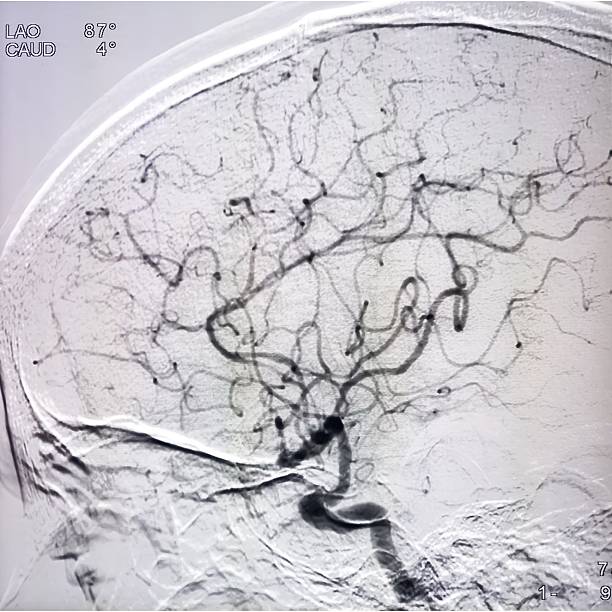

뇌경색은 뇌혈관이 막히면서 해당 부위에 혈액이 공급되지 않아 뇌세포가 손상되는 질환이에요.

**‘허혈성 뇌졸중’**이라고도 하며, 전체 뇌졸중의 약 **70~80%**를 차지할 만큼 흔한 형태입니다.

보통은 고혈압, 당뇨, 고지혈증, 흡연, 심장질환 등이 주요 원인으로 작용하죠.